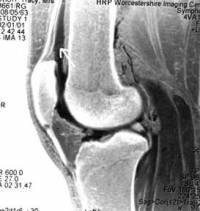

The space inside the knee joint is larger than one might expect, due to an extension of the joint cavity a handsbreadth above and behind the knee cap (the black space where the arrow is pointing).

During arthroscopy, clear fluid is pumped under pressure into the joint cavity to blow it up and make more space for the surgeon to see all the internal structures.